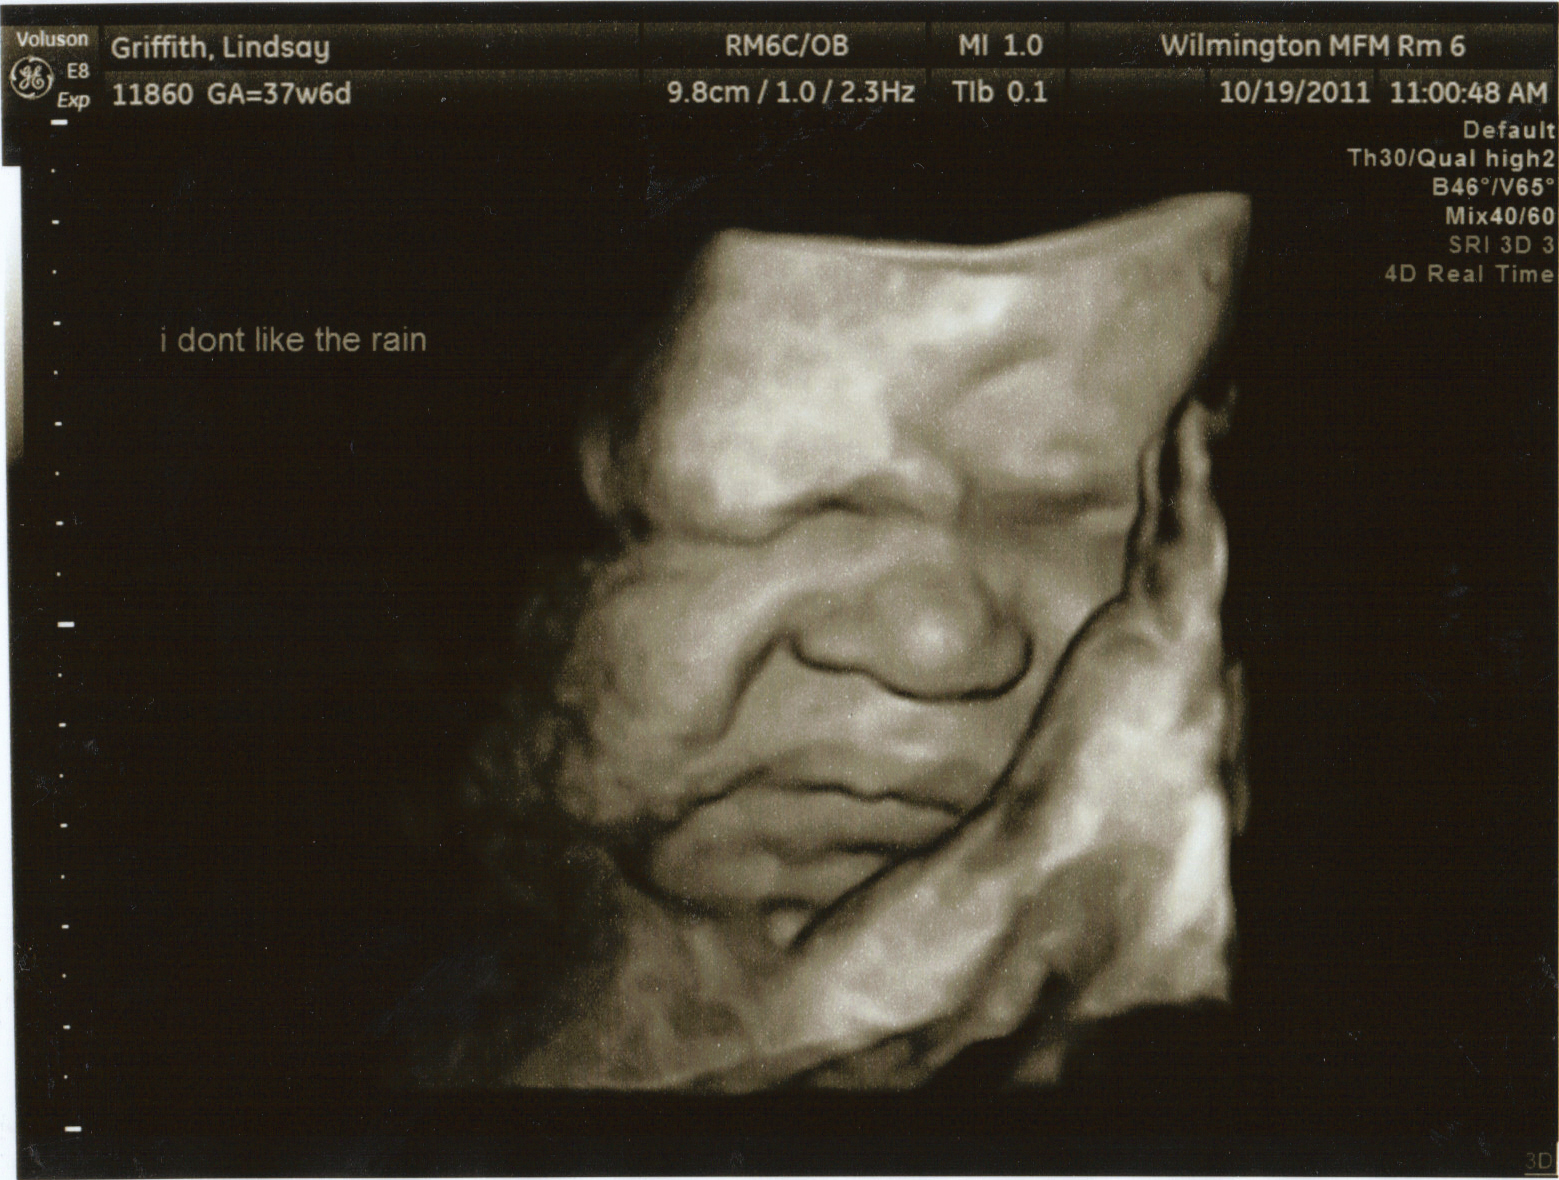

CHUBBY CHEEKS!!

35 weeks...September 29

So today was our repeat ultrasound to make sure the fluid around Silas (AKA Baby G) wasn't increasing. It thankfully decreased to 22...it was 27 and normal is below 20. However, we had another test called a biophysical profile (BPP), which checks for movement, tone, and breathing movements in him. Well, he was not being too cooperative and didn't show the sonographer any breathing movements so off to the hospital we went for extended monitoring. In the end everything was ok and we got to go home, but we will return the next day for ANOTHER ultrasound.